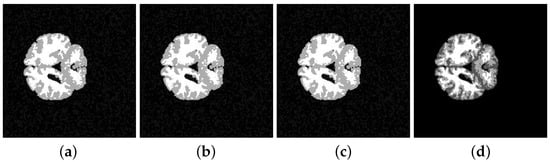

| E-measure | 0.5374 ± 0.0763 | 0.5381 ± 0.0750 | 0.5363 ± 0.0742 | 0.5348 ± 0.0761 |

| Subject | Method | JS | DSC | Sensitivity | Specificity | Accuracy |

|---|---|---|---|---|---|---|

| K-means | % | |||||

| 202-3 | ||||||

| 0.8938 | 0.9486 | |||||

| K-means | ||||||

| 205-3 | ||||||